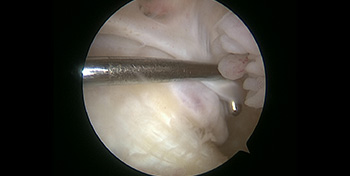

- Arthroscopy – Arthroscopic equipment used to perform keyhole surgery and visualize the ankle joint.

- Day 0 – Images obtained during surgery – Note the scar tissue and bone spur at the front of the ankle.